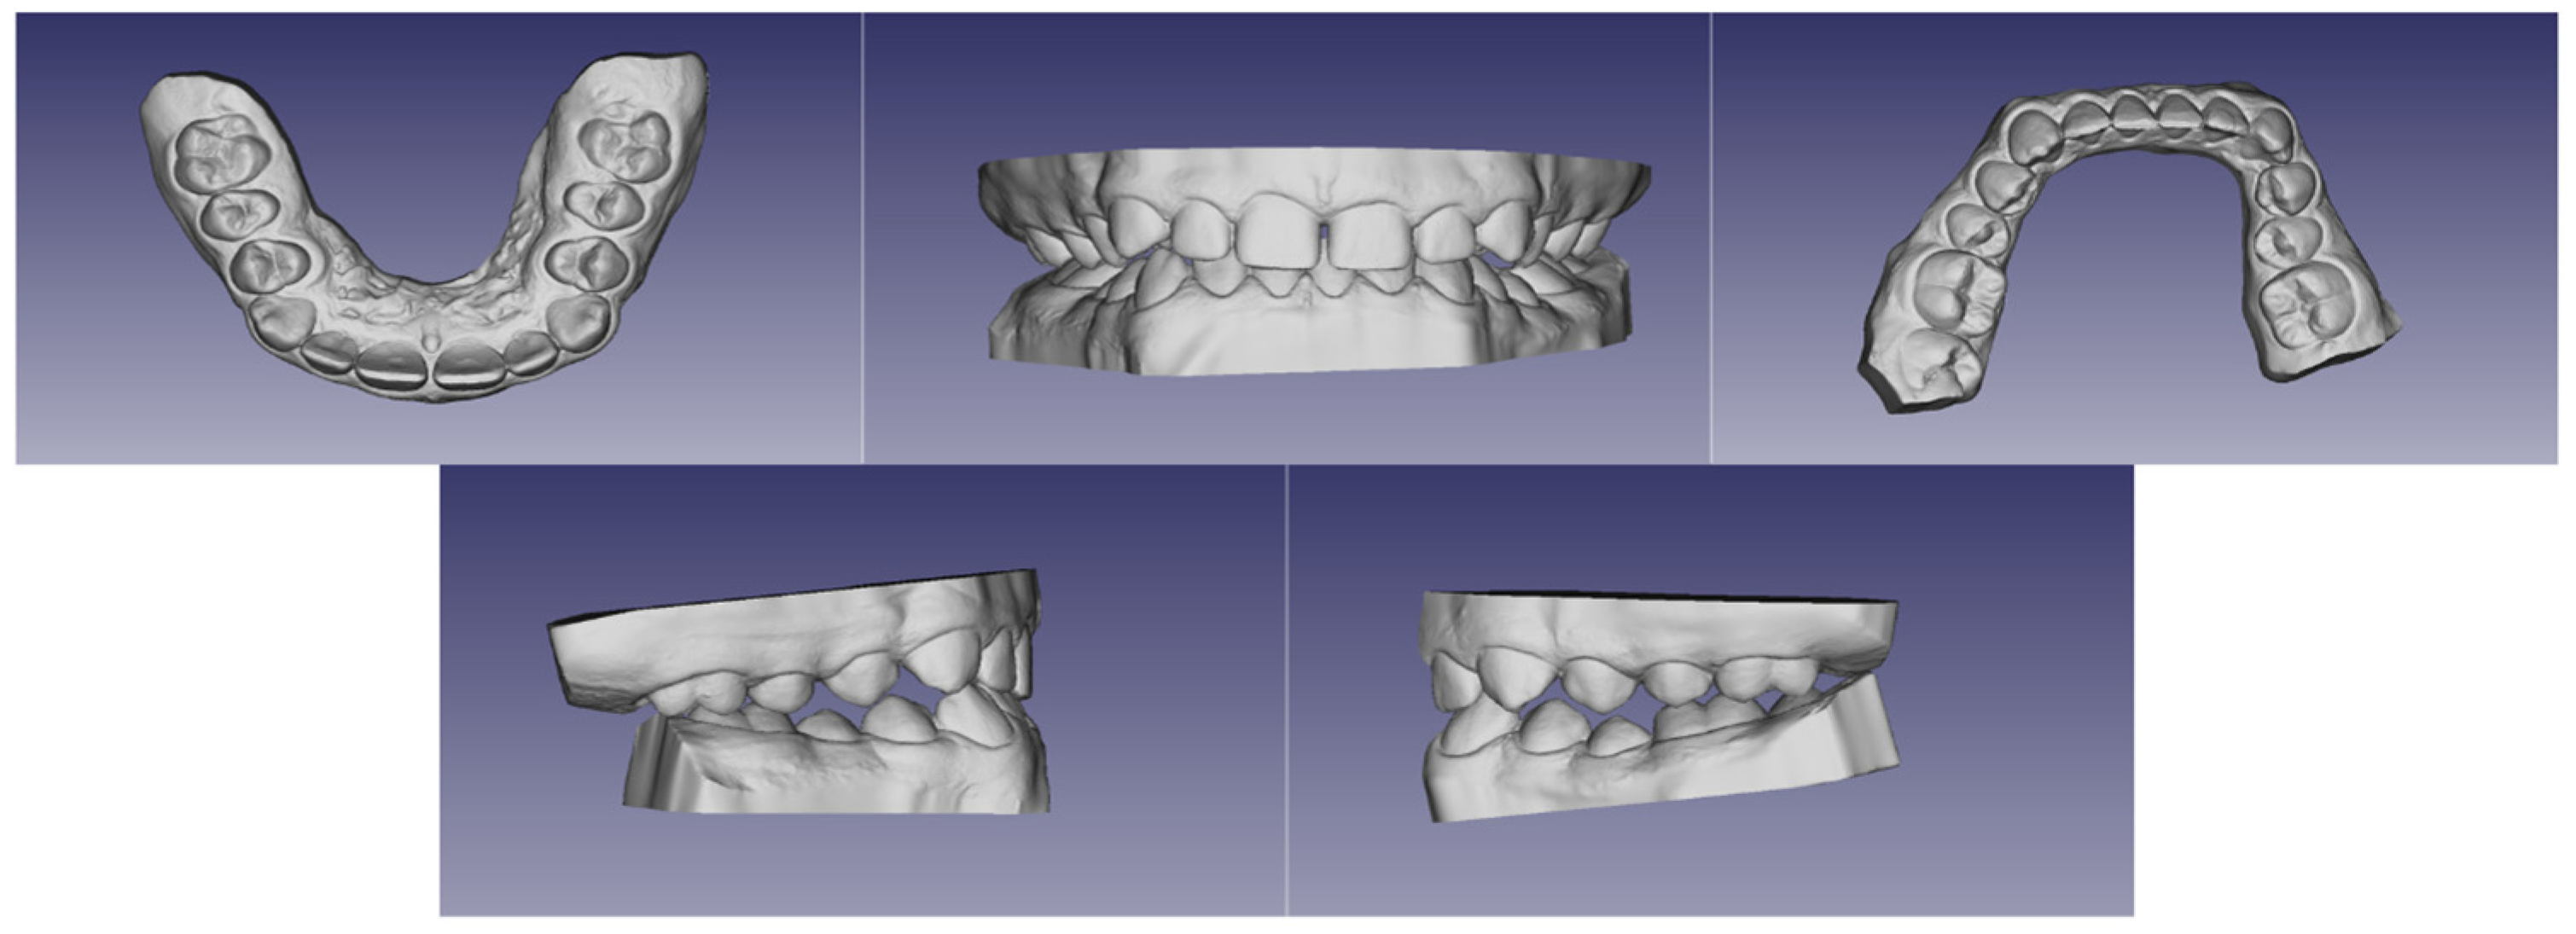

| Characteristics | Previous Studies | This Study |

|---|---|---|

| sex | 3 boys, 1 girl | a boy |

| mental retardation | 4/4 | + |

| speech disorders | 3/4 | + |

| facial dysmorphism | 4/4 | + |

| malocclusion | 4/4 | + |